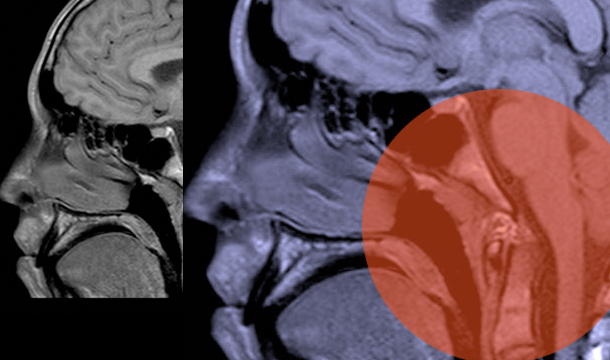

Screening for Chiari I Malformation

Karin M. Muraszko, MD, FAANS; Hugh J. L. Garton, MD, MHSc, FAANS; and Cormac O. Maher, MD, FAANS—Who should be screened for Chiari Malformation Type I (CM)? It is impossible to have a “cookbook” standard that will apply to everyone. Consideration of symptomatology in relation to known associated conditions should lead the clinician to consideration for obtaining an MRI scan to diagnose a CM. Diagnosing Chiari I Malformation The symptoms associated with CM are, in many cases, non-specific and protean. Based on reviews of the extensive literature on CM, it is apparent that most neurological symptoms have at some point been associated with CM. The most common symptom is clearly headaches, but any number of brainstem and spinal cord associated symptoms has been attributed to CM in some patients. Many symptoms are, by themselves, commonly found in those with other neurological disorders or conditions. Therefore, the diagnosis of a symptomatic CM requires the clinician to actively include CM in the differential diagnosis, while also being careful to include other conditions that may mimic Chiari symptoms. The decision to perform an MRI scan, particularly to rule out a CM, should start with a…